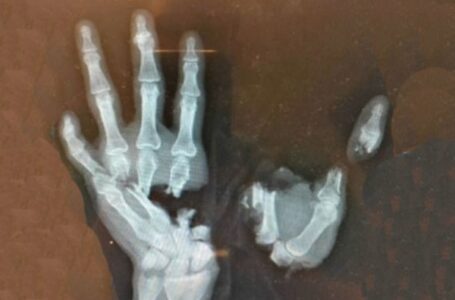

Ministarstvo unutrašnjih poslova (MUP) apelovalo je na građane, a posebno mlade, da ne koriste petarde i slična pirotehnička sredstva tokom praznika. MUP ih je na Fejsbuku pozvao da ne dozvole da praznici postanu tragedija, te…